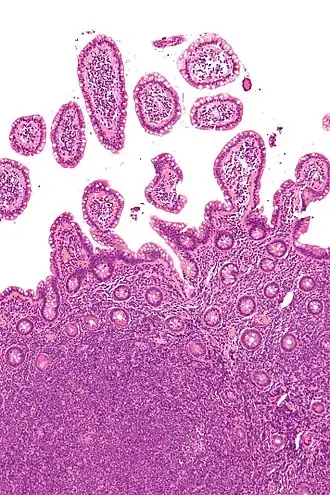

Biopt van mantelcellymfoom in de kronkeldarm (H&E-kleuring)